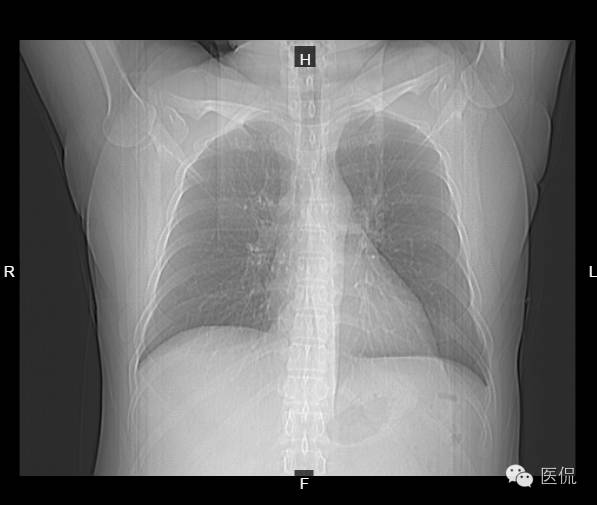

患者信息:男,37岁,体检

检查方法:胸部CT平扫

影像所见:

CT平扫胸廓对称,肺窗显示两肺纹理清晰,走向分布无异常,肺实质未见渗出或占位性病变。纵隔窗显示两肺门无增大,气管支气管通畅,纵隔未见肿大淋巴结,心脏及大血管走行未见明确异常,胸膜、肋骨及胸壁软组织未见异常。肝实质密度减低,CT值46HU。

诊断意见:

1、胸部CT扫描未见异常。

2、脂肪肝。